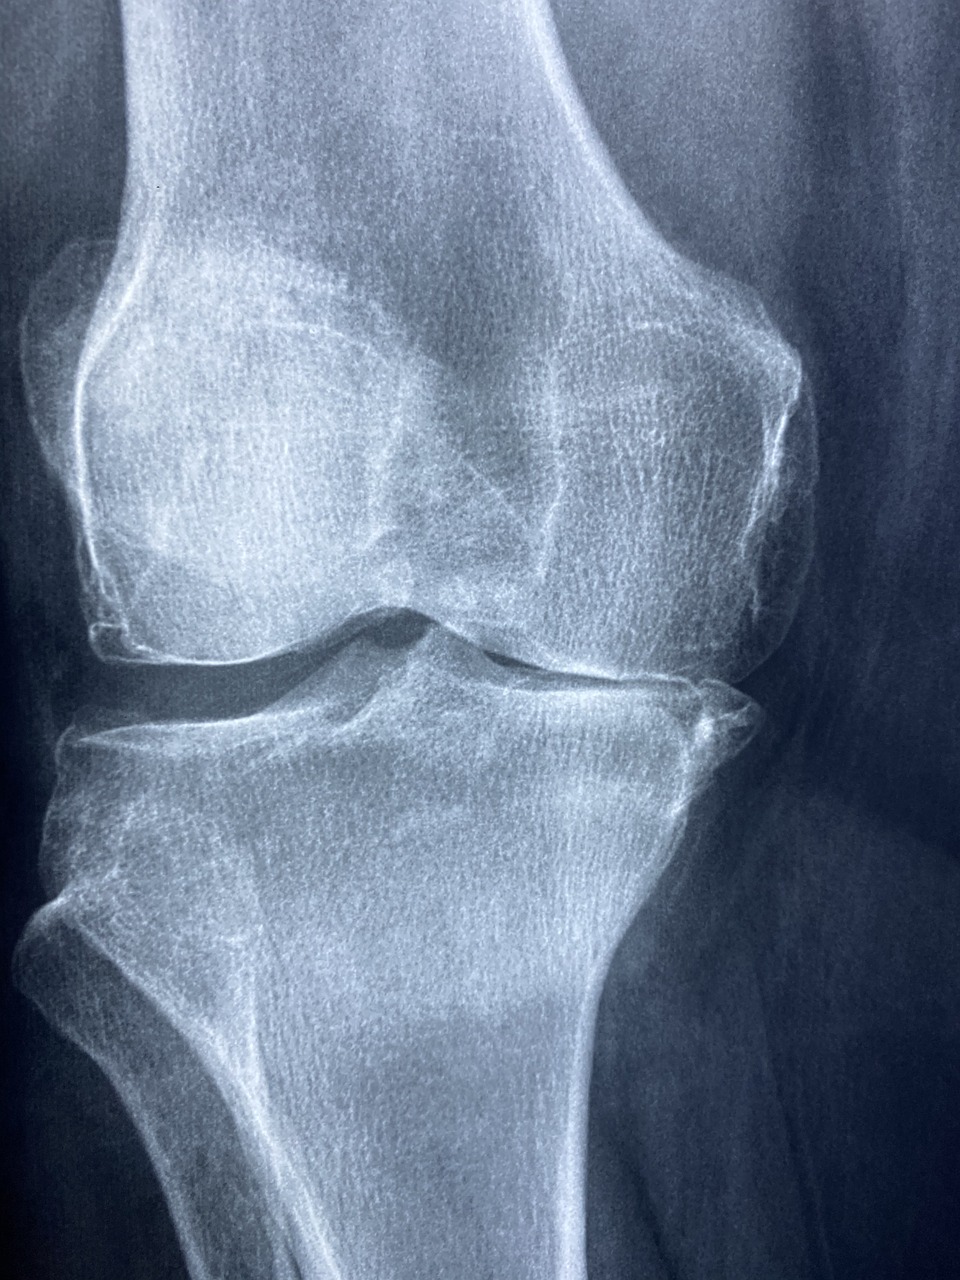

무릎

[KNEE CLINIC]

무릎은 걷기, 뛰기, 앉기 등 일상적인 움직임을 가능하게 하는 중요한 관절입니다.

하지만 관절연골결손, 반월판연골손상, 전후방십자인대파열, 원판형발달연골 같은 질환은 초기 통증을 간과할 경우 만성적인 문제로 이어질 수 있습니다.

조기에 정확한 진단과 치료를 통해 무릎의 기능과 건강을 되찾는 것이 무엇보다 우선입니다.

무릎 관절염

무릎 관절염은 무릎 관절을 덮고 있는 연골이 손상되거나 닳아 없어지는 질환입니다.

주로 외상, 반복적인 관절 사용, 퇴행성 또는 염증성 관절염으로 인해 발생하며, 연골은 자연 재생이 어려워 손상이 진행될수록 통증과 관절 강직이 심해질 수 있습니다. 이 질환은 초기에는 무릎의 뻐근함이나 가벼운 통증으로 나타나지만, 시간이 지나면서 보행이 어려워질 정도의 심각한 증상으로 진행될 수 있습니다.